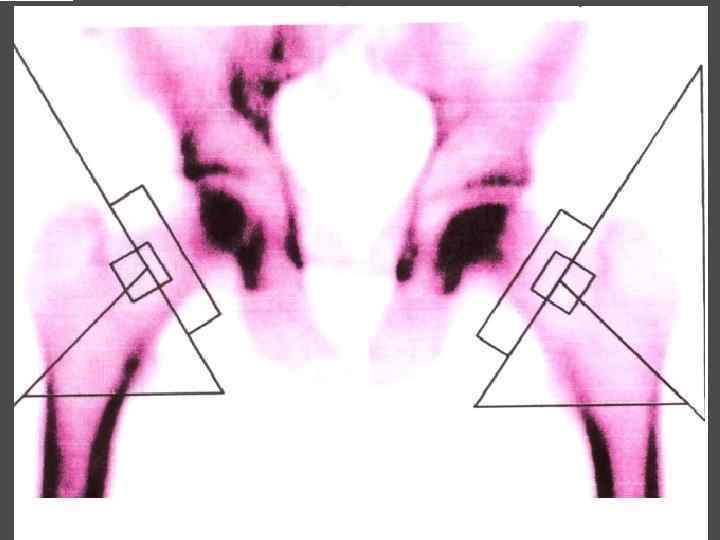

МЕТОДЫ ИССЛЕДОВАНИЯ ► Определения уровня кальция крови, паратгормона ► Сцинтиграфия паращитовидных желез с Тс99 ► УЗИ ► ПТАБ ► КТ, МРТ ► Денситометрия